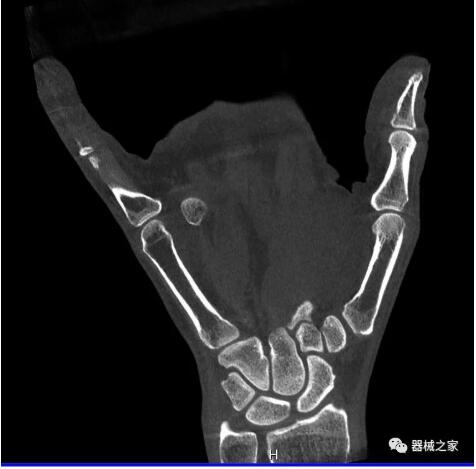

以上介紹的CT均來自國外同一家公司,這些CT均配置了可視化軟件,可以進(jìn)行切片、3D重建以及大型CT附帶的所有典型的操作功能。

以下是這些“特立獨(dú)行”的CT所拍出來的圖像: